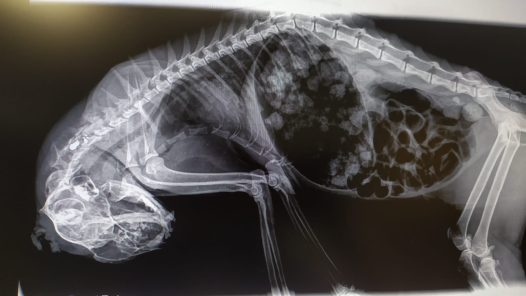

Agressió a una colònia de gats de Tortosa. L’entitat Progat ha denunciat als Mossos d’Esquadra l’atac a trets contra cinc felins al barri de Ferreries. Lara Mangrané.